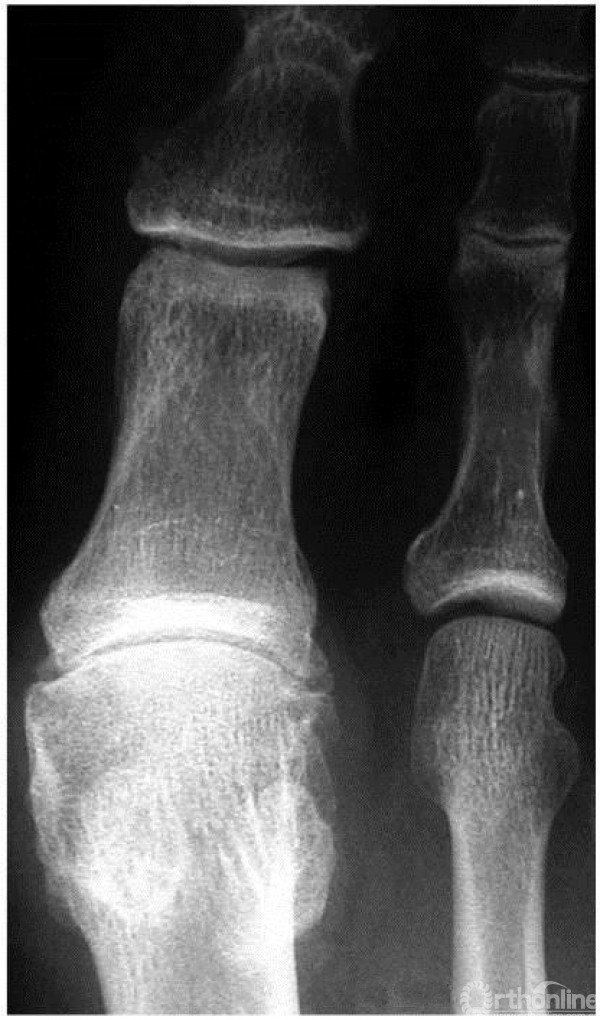

1期:正位x线上,箭头示外侧小的骨赘形成,关节间隙完好

2期:正位X线上,关节外侧缘大量骨赘形成,跖骨头轻度扁平,关节间隙轻度狭窄,伴有骨硬化

3期:正位X线上,关节间隙广泛变窄,籽骨形态不规则

4期:关节炎表现较3期更为明显、严重(3,4期影像学表现可以差别不大,但临床表现却相差很大)